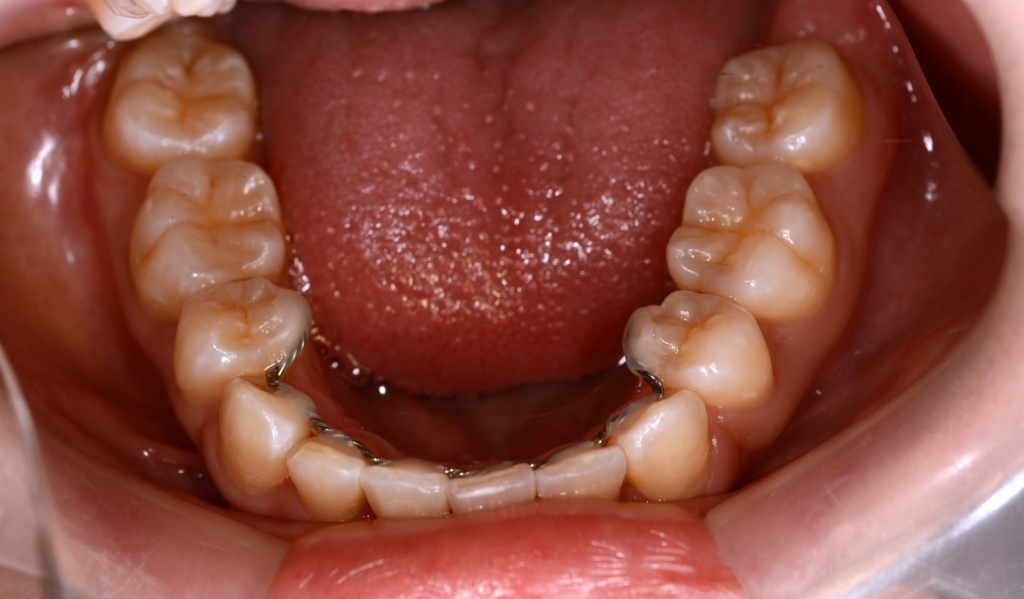

【保定】 上下ともフィックスタイプ&クリアリテーナー

あらためて、矯正治療前後の歯並びと口元の変化を比べてみましょう。

まずは、歯並びの変化です。